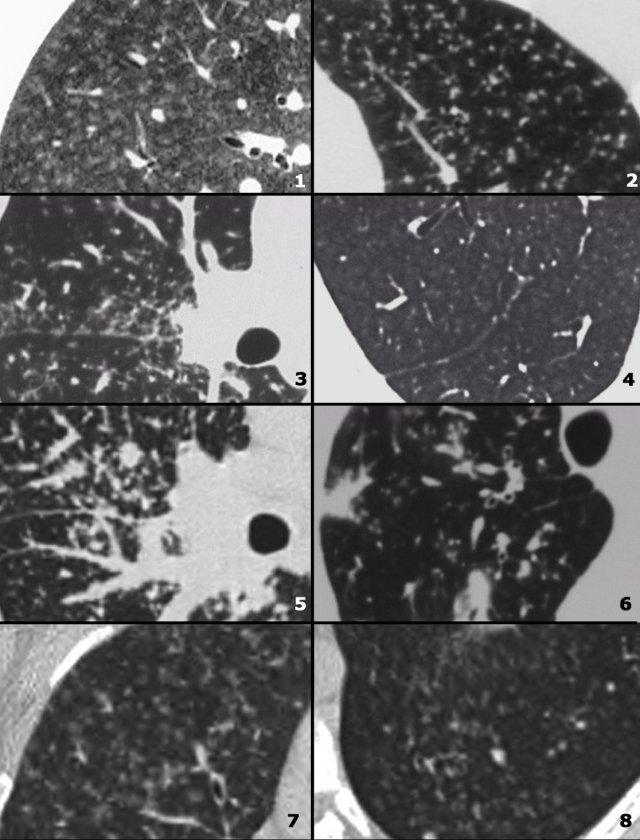

Hình ảnh

- Lao kê – các nốt nhỏ đồng đều phân bố ngẫu nhiên

- Di căn – các nốt có kích thước khác nhau phân bố ngẫu nhiên.